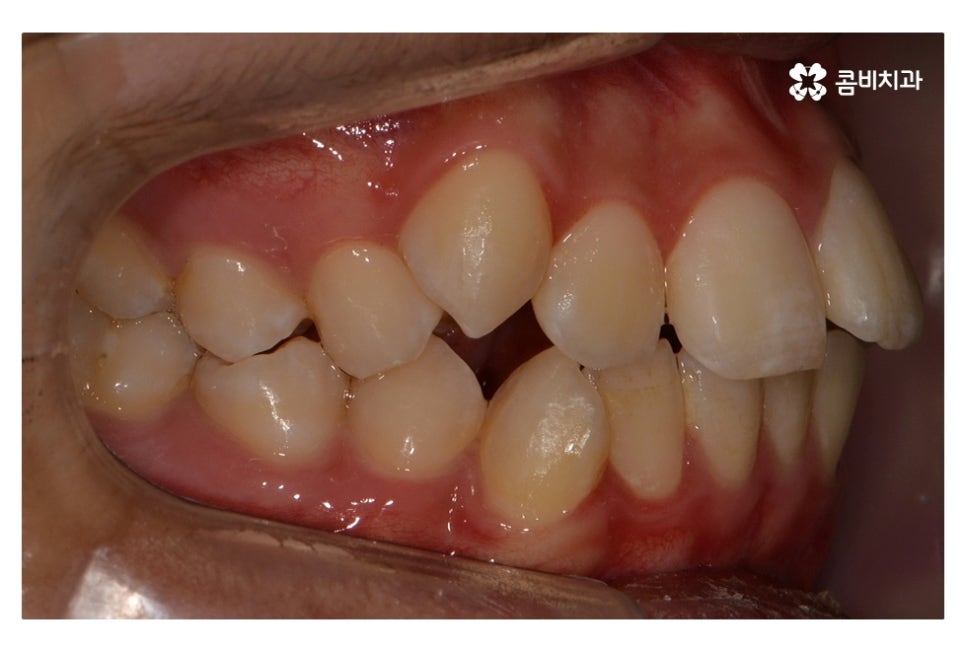

위 환자분의 경우 발치가 진행된 사례로 치아의 이동 공간을

고려할 때 발치가 필요했고 환자분도 보다 나은

심미성을 위해서 동의한 상황이라고 할 수 있어요.